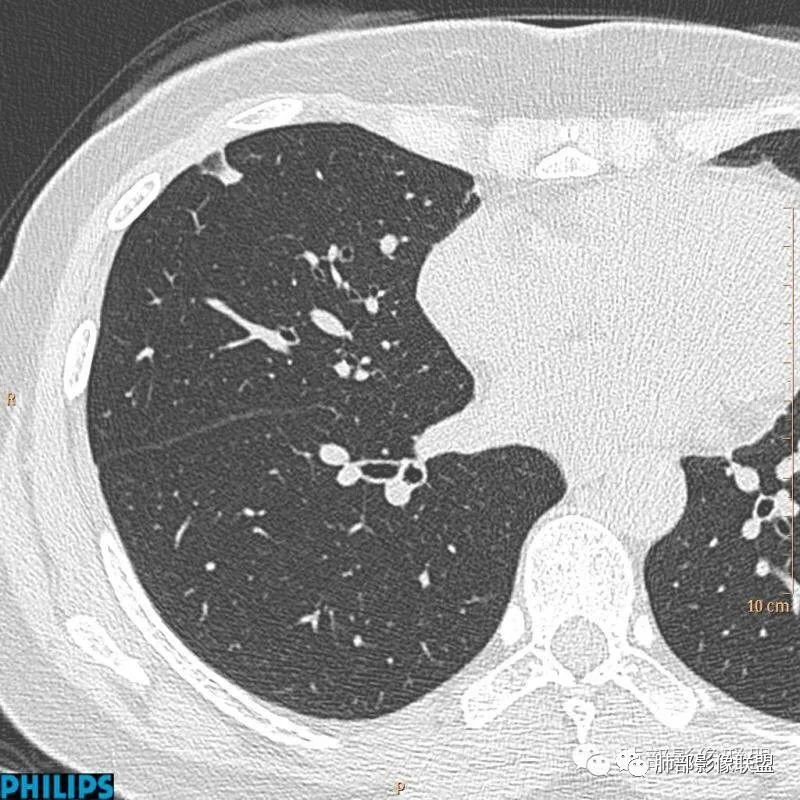

病例四:

以上病例,有什么共同点?1、病灶均位于胸膜下或叶间胸膜下;

2、病灶边缘多平直,大部分呈三角形,部分呈椭圆形;

3、病灶边缘见一条或数条细线与胸膜相连。

正常情况下,肺内淋巴结是不显示的,一般是慢性炎症所致,老年人和吸烟者多见。影像上常见于胸膜或叶间胸膜下,迄今为止,所有的报道均距胸膜或叶间胸膜小于2.0cm以内。也可以表现为与胸膜或叶间胸膜相贴的结节。绝大多数位于中下叶(气管隆突水平以下),上叶也可见到,但较少见。

长径均小于12mm。典型的形状为三角形,也可以为梭形、圆形或椭圆形。诊断的关键在于见到1-5条细线与胸膜、叶间胸膜或静脉相连,有时状如坐落于电路板的“二极管”,但以薄层CT显示为佳。有作者病理对照线状影为小叶间隔,有作者病理对照为淋巴管。其实不矛盾,因为淋巴管走行于小叶间隔内。

对怀疑肺内淋巴结的病例,必须行薄层扫描,推荐1.5mm及以下层厚。因为在5mm层厚图像,肺内淋巴结可以由于部分容积效应表现为磨玻璃密度结节,而且对线状影及病变形状的显示也欠清晰。

诊断肺内淋巴结最关键指出在于薄层扫描见到细线状影与胸膜、叶间胸膜及肺静脉相连。